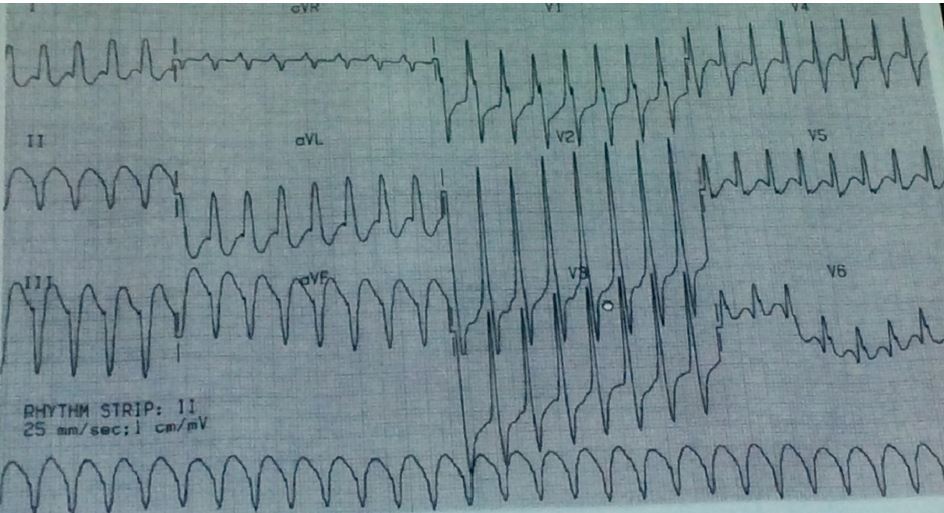

Ventricular Tachycardia

Hypokalemia turning to Ventricular Fibrilation